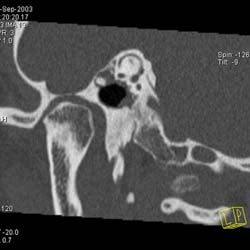

Рис. 10. Принципы КТ высокого разрешения (КТВР) на примере исследования пирамиды височной кости. Применены тонкие срезы (0.5 мм) и "острый" алгоритм реконструкции (кернель 90). (Слева) отчетливо видны элементы внутреннего уха - улитка, полукружные канальцы. (В центре) показана проекция продольного сечения височно-нижнечелюстного сустава. (Справа) - холестеатома.